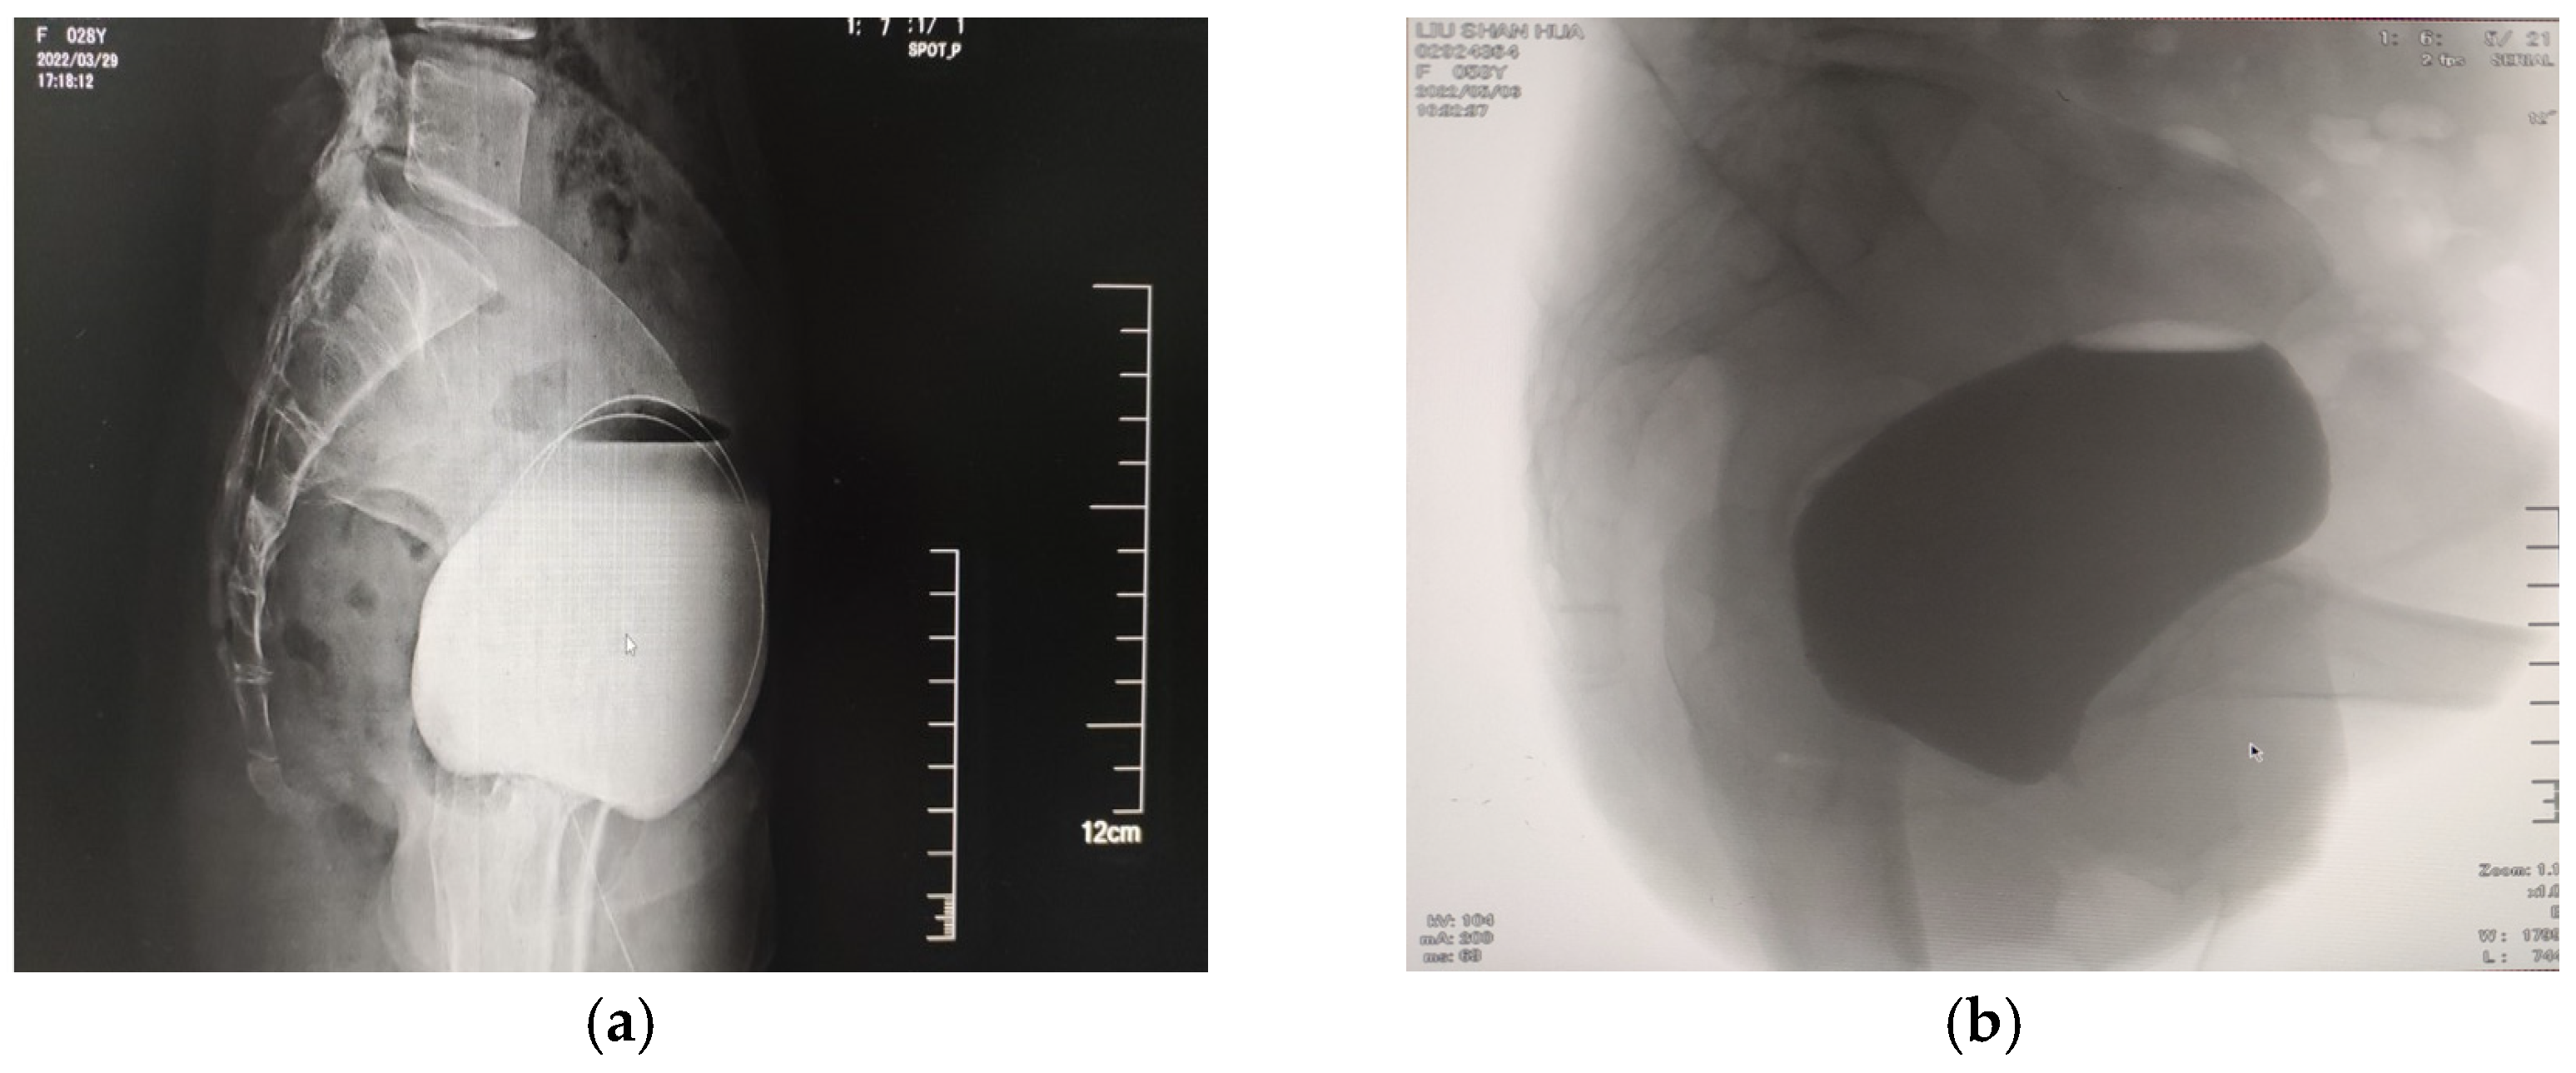

3. Anatomical Factors Affecting the Urethra (Figure 2)